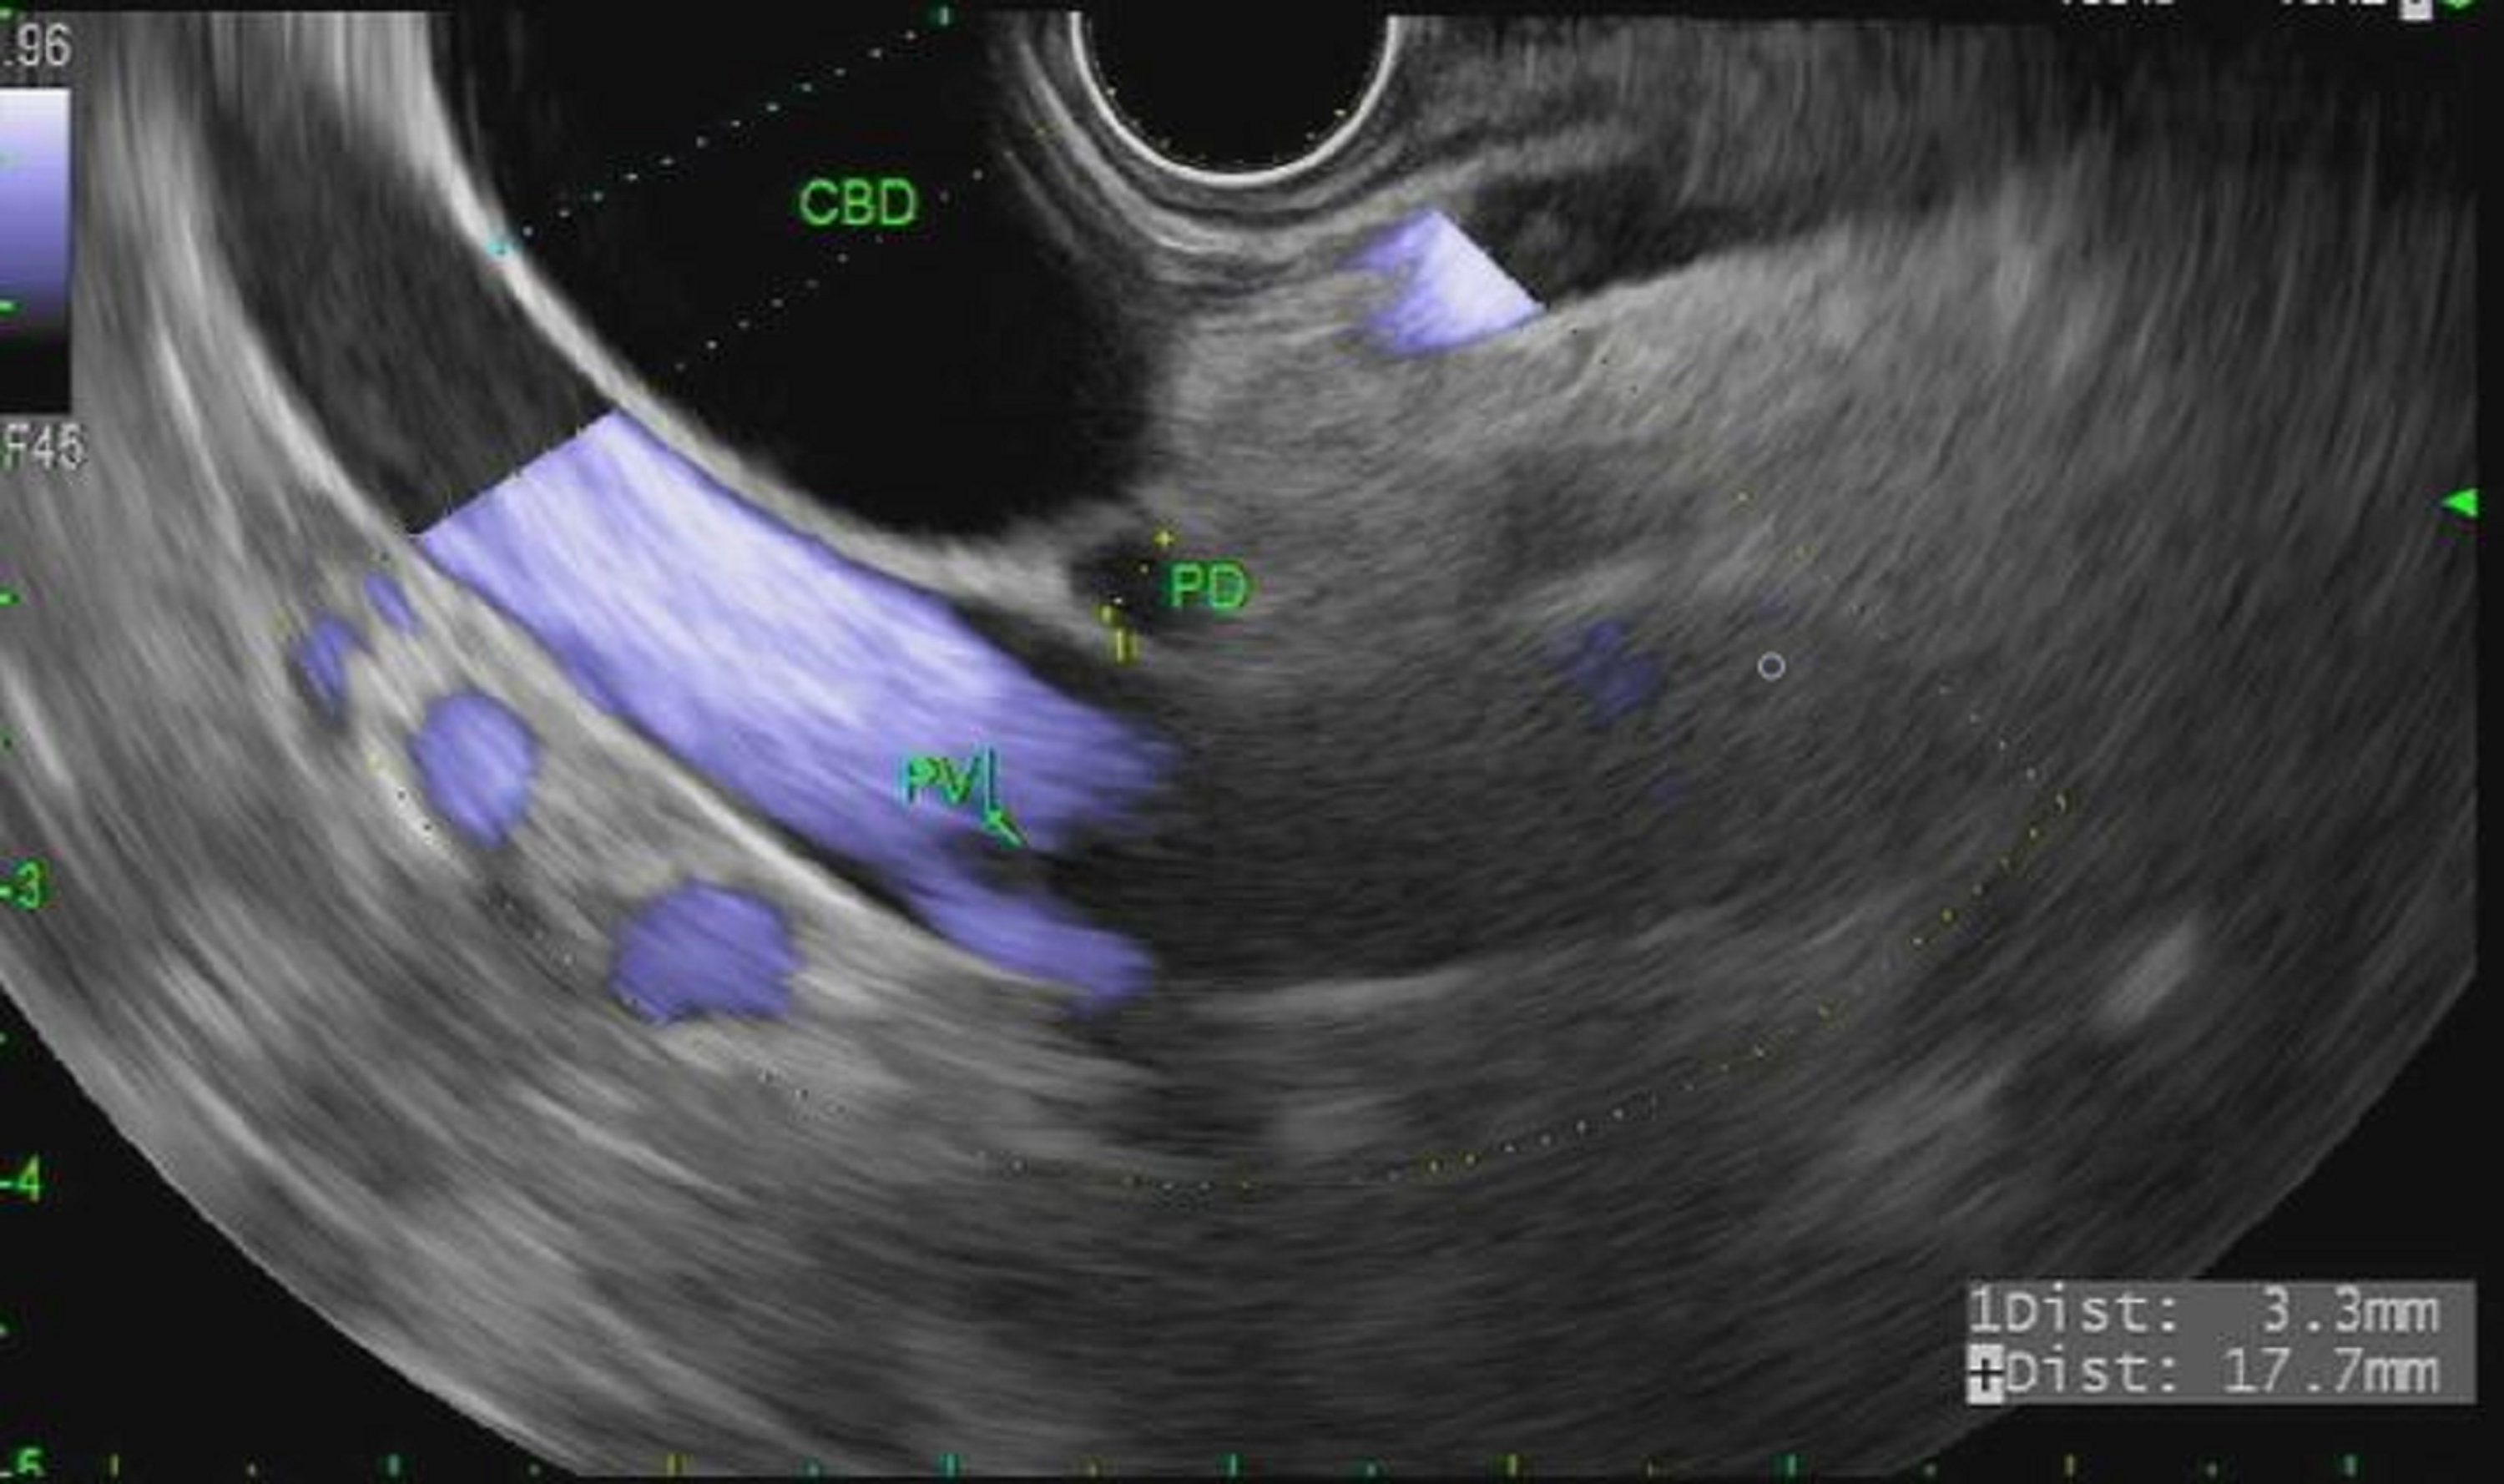

Endoscopic ultrasonography (EUS)guided biliary drainage (EUS Endoscopic Biliary Decompression Currently, ercp remains the standard of care for biliary decompression. In future, it is possible that eus guided transmural biliary drainage may replace ercp for certain. Endoscopic retrograde cholangiopancreatography (ercp) and stent placement are considerably safer than surgical. A recently report titled “timing of endoscopic retrograde cholangiopancreatography in the treatment of acute cholangitis of different. Endoscopic Biliary Decompression.